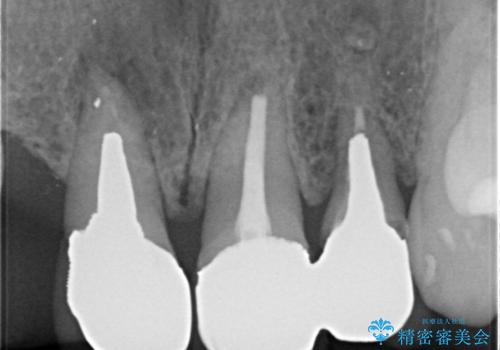

根の状態も良くなかったため、根管治療から行うこととなりました。

左上2番の歯は歯根が割れていたため抜歯し、入れ歯をブリッジに変えていきます。

- 右上1左上1:根管治療(リトリートメント)+土台(ファイバーコア)/99,000円×2本+22,000円×2本 右上123左上123:仮歯+ジルコニアクラウン(スタンダード):11,000円×6+121,000円×6 計1,034,000円(税込)費用は治療当時の料金となります